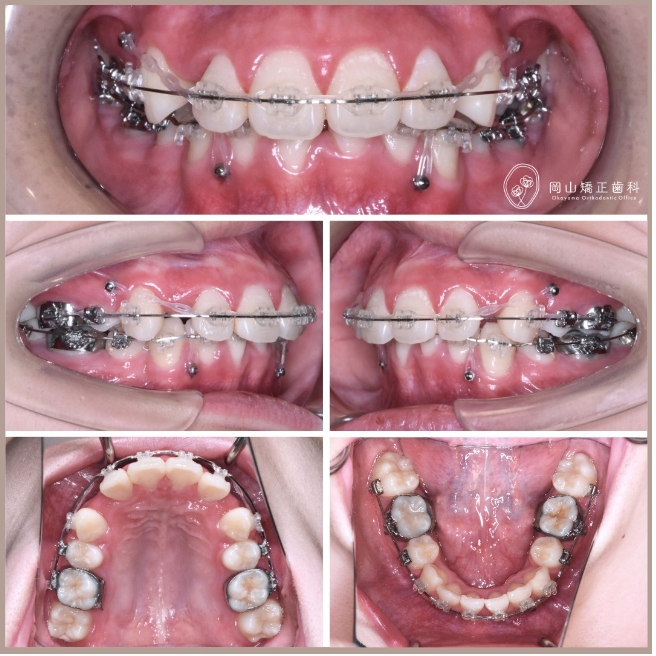

症例01

症例詳細

| 診断名 | 叢生と過蓋咬合を伴う上顎前突症例 |

| 治療装置 | マルチブラケット矯正装置(ワイヤー矯正) |

| 抜歯部位 | 上顎両側第1小臼歯、下顎両側第1小臼歯 |

| 治療期間 | 2年11ヶ月 |

治療の過程